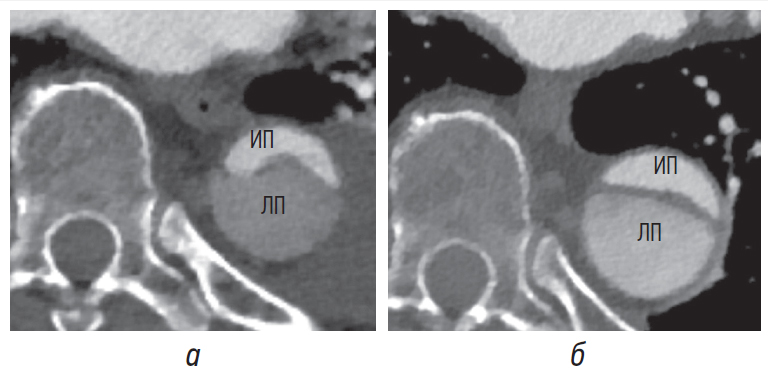

Наиболее часто определяемым признаком, который позволяет надежно отличить ложный просвет от истинного, является так называемый признак «клюва» [4, 5, 8]. Он визуализируется в поперечном сечении аорты и представляет собой острый угол при диссекции аорты. Грани угла формируются наружной стенкой аорты на краю ложного просвета и интимомедиальным лоскутом (рис. 4, а, б).

Рис. 4. Признак «клюва» в восходящем отделе аорты (а), в нисходящем отделе аорты (б) (белые стрелки) без признаков тромбоза. Интимомедиальный лоскут отмечен черными стрелками. ИП — истинный просвет, ЛП — ложный просвет ЛП

Пространство, образованное острым углом, может быть заполнено гиперденсным содержимым (повышение плотности крови вследствие контрастного усиления) (рис. 4, а, б). При заполнении этого пространства гиподенсным содержимым, соответствующим частичному/полному тромбозу, угол притупляется (рис. 5, а, б) [4, 5, 8]. Признак «клюва» наблюдается только в ложном просвете во всех случаях острой и хронической диссекции [8].

Рис. 5. Признак «клюва» при частичном (а) и тотальном тромбозе (б) в нисходящем отделе аорты (белые стрелки). ИП — истинный просвет, ЛП — ложный просвет